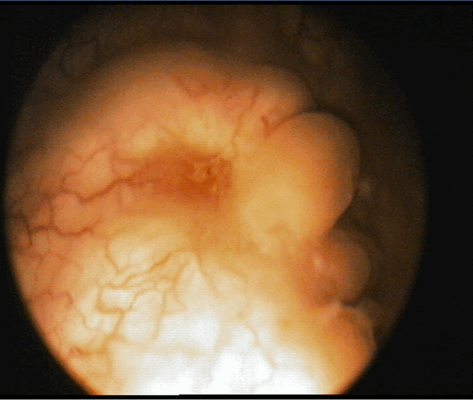

Цистоскопическое обследование пациента С.

Цистоскопическая картина солидного образования, вдающегося в полость мочевого пузыря в виде массивных бугристых масс, покрытых отечной слизистой оболочкой

По данным ультрасонографии ретенционные изменения верхних мочевых путей с обеих сторон были выявлены у пациентки О., 35 лет, (чашечки и лоханка справа 16 и 32 мм, слева – 15 и 35 мм соответственно, у остальных пиелокаликоэктазии не было. Больным была выполнена цистоскопия, по данным которой в 3 случаях определялось стелящееся солидное образование в диаметре около 8 см (пациентка О., 35 лет), 5,6 (пациент М., 43 лет) и 2,8 см (пациент С., 56 лет) с явлениями буллезного отека, распада, кровоизлияний и инкрустацией мочевыми солями Образования предположительно характеризовались инфильтративным характером роста.